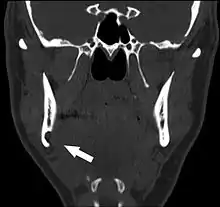

عادة ما يتم اكتشاف تجويف ستافني عن طريق الصدفة خلال التصوير الشعاعي للأسنان الروتيني.[3] في صورة الأشعة يظهر بشكل تجويف محدد أحادي مستدير منفذ للأشعة، يتراوح حجمه بين 1 و 3 سم، عادة بين العصب السنخي السفلي (IAN) والحدود السفلية للفك السفلي الخلفي بين الضروس وزاوية الفك. انها واحدة من عدد قليل من الآفات المشعة التي يمكن أن تحدث تحت العصب السنخي السفلي. الحدود محاطة بشكل جيد ولن يكون لها أي تأثير على الهياكل المحيطة. سيُظهر التصوير المقطعي المحوسب (CT) تجويفًا ضحلًا عبر القشرة الوسطية للفك السفلي مع حافة محاطة ولا توجد تشوهات في الأنسجة الرخوة، باستثناء جزء من الغدة تحت الفك السفلي. يمكن أن تخلق الأورام مثل السرطان الحرشفي الخلايا النقيلي إلى العقد اللمفاوية تحت الفك السفلي أو ورم الغدد اللعابية، مظهرًا مشابهًا ولكن نادرًا ما يكون لها حدود محددة بشكل جيد ويمكن عادةً أن يتم تحسسها في أرضية الفم أو مثلث تحت العنق تحت الفك السفلي ككتلة صلبة. التصوير المقطعي المحوسب والفحص السريري عادة ما يكون كافيا للتمييز بين هذا وتجويف ستافني. يميل تجويف ستافني أيضًا إلى عدم الزيادة في الحجم أو التغيير في المظهر الشعاعي بمرور الوقت (ومن هنا يأتي المصطلح "كيس عظمي ثابت")، ويمكن استخدام هذا للمساعدة في تأكيد التشخيص. لا يتطلب الأمر عادة خزعة من الأنسجة، ولكن إذا تم عملها فإن مظهر الأنسجة هو عادة أنسجة الغدة اللعابية الطبيعية. في بعض الأحيان تكشف عينة من تجويف ستافني عن تجويف خالٍ (ربما بسبب إزاحة الغدة في وقت أخذ الخزعة)، أو محتويات أخرى مثل الأوعية الدموية أو الدهون أو اللمف أو الأنسجة الضامة. قد يتطلب تجويف الفك السفلي اللساني الأمامي خزعة للتشخيص الصحيح في هذا المكان الغير عادي. قد يركب التجويف المنفذ للأشعة على الأسنان الأمامية السفلية ويحدث خطأ تشخيصي بأنه لآفة سنية المنشأ. في بعض الأحيان قد يقطع التجويف الحد السفلي للفك السفلي، وقد يكون جسه ممكن. قد يستخدم أحيانا تصوير القناة اللعابية للمساعدة في إظهار الأنسجة الغدة اللعابية داخل العظام.